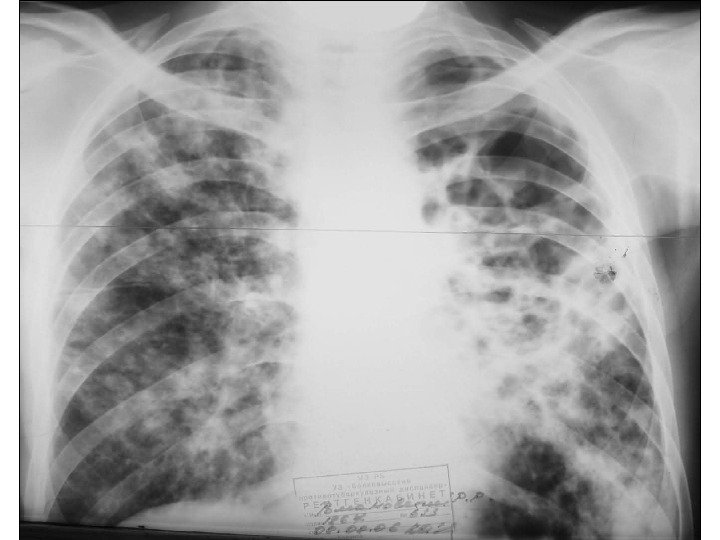

Инфильтративный туберкулез легких рентгенологическая картина Лобит • распространенное негомогенное затемнение в пределах доли легкого • расположение и форма тени зависят от того, какая доля поражена • границы подчеркнуты плевральными листками • томографически — почти однородная тень, полости распада • очаговая диссеминация в противоположном легком

Казеозная пневмония диагностика • анамнез • отрицательная анергия при р. Манту • обильное выделение МБТ • лейкоцитоз, лимфопения, сдвиг влево, увеличение СОЭ до 30 -60 мм / ч Рентгенологическая картина: при лобарной форме — затемнение в пределах доли, неоднородное, с просветлениями неправильной формы, затем формируются тонкостенные каверны различных размеров при лобулярной форме — множество крупноочаговых теней и фокусов неправильной формы, без четких границ, средней или высокой интенсивности, склонных к слиянию; — формирование крупных (гигантских) каверн и мелких (дочерних) каверн